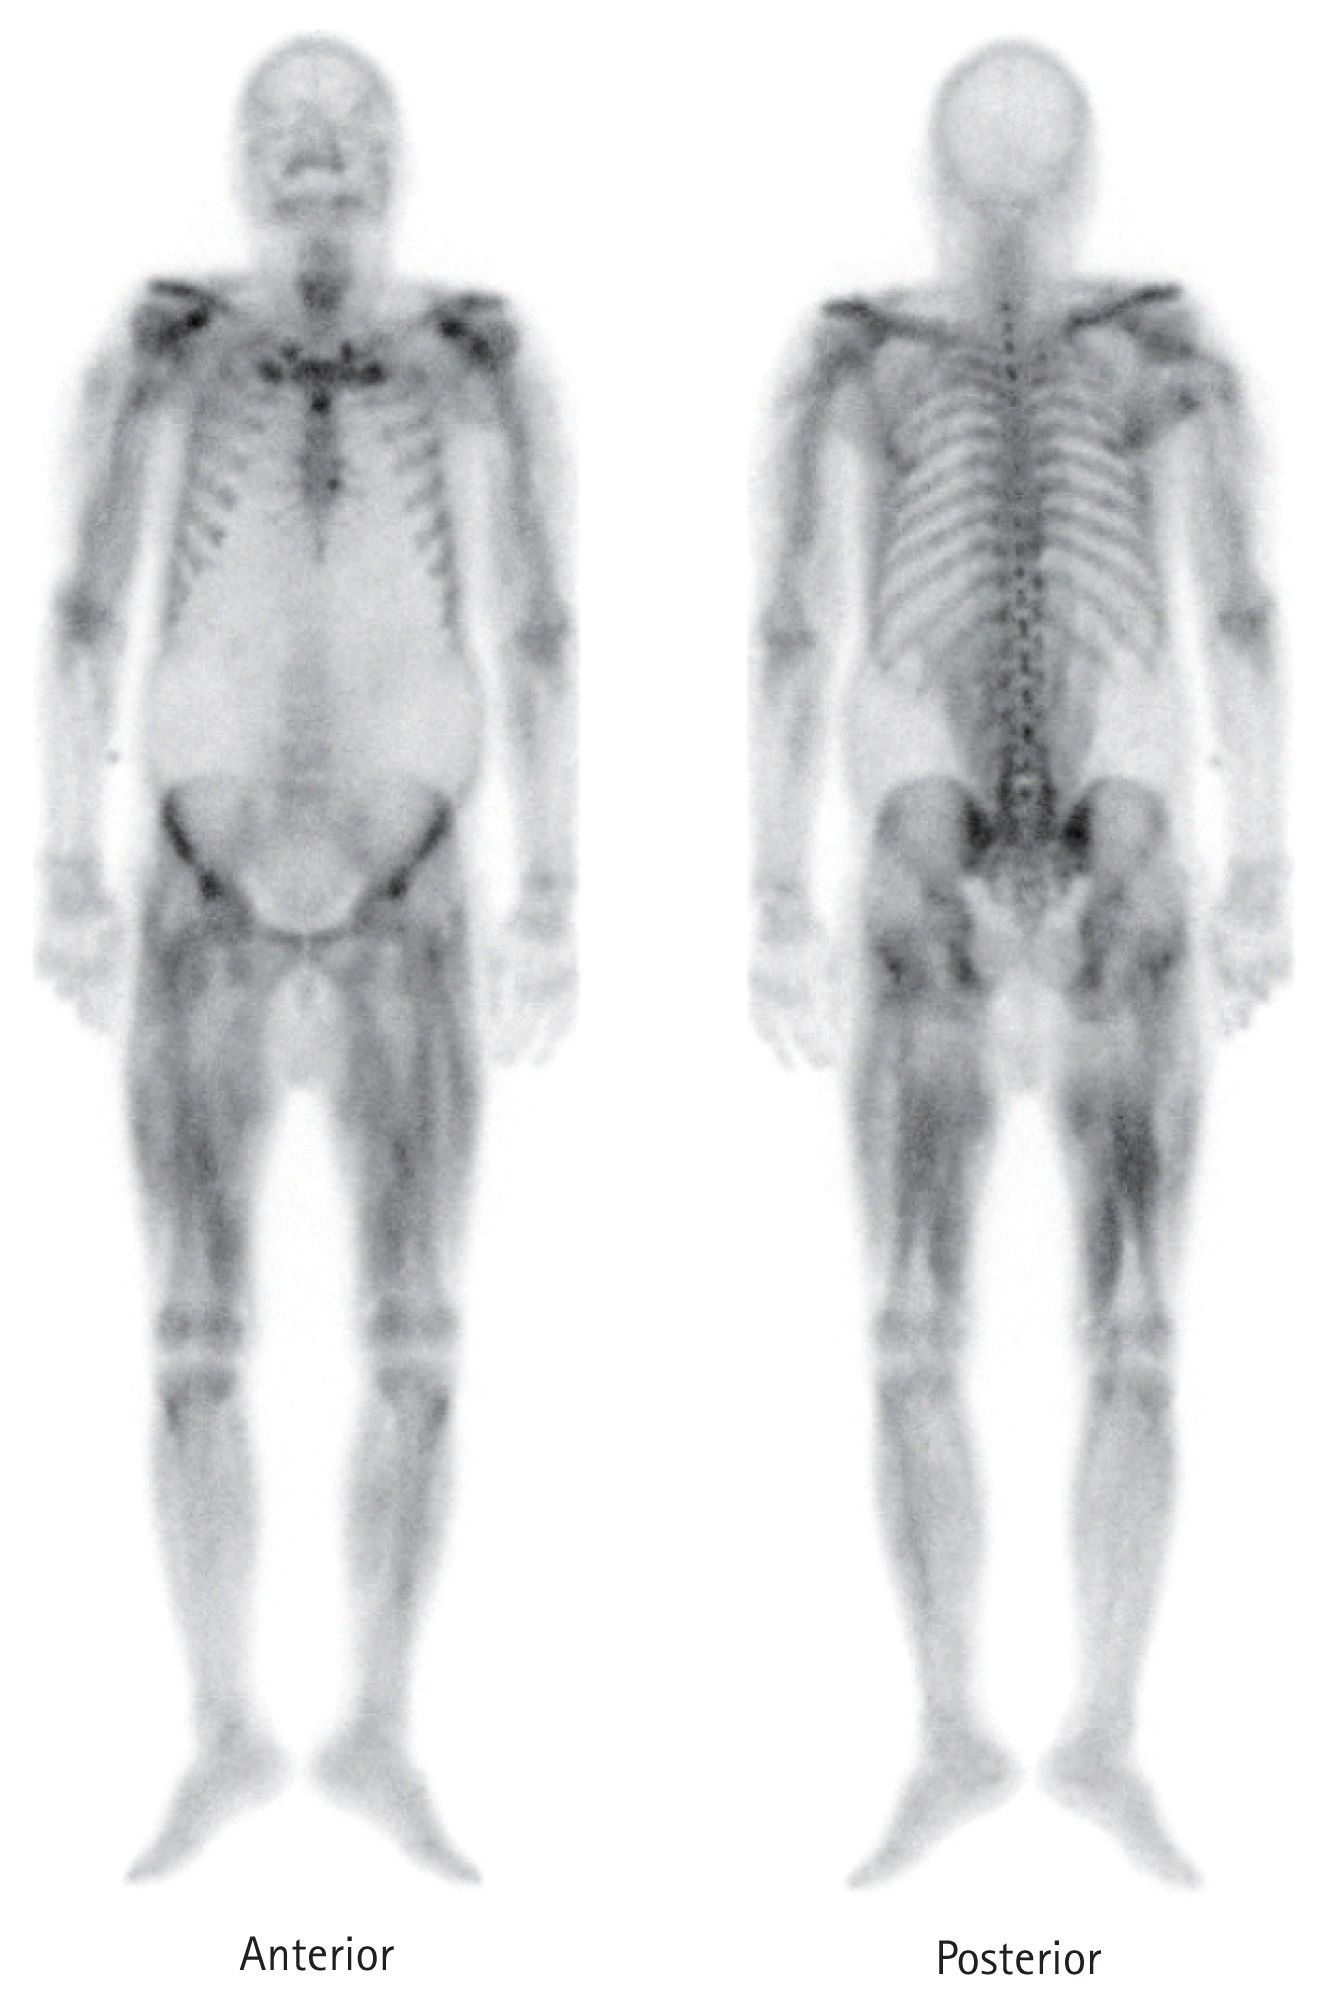

A 63-year-old male on hemodialysis, presented to the emergency department with bilateral thigh pain and weakness. He had been taking pregabalin 50mg once daily for uremic pruritus at the local dialysis center. He recently visited the dermatology clinic for worsening symptoms and added 75mg of pregabalin to his daily dose, for a total of 125 mg per day. After three days, he developed bilateral thigh tenderness and weakness. Laboratory findings showed elevated levels of creatinine kinase at 17,036 U/L (reference range: 5–217 U/L) and myoglobin > 20,000 ng/mL (reference range: 3–110 ng/mL). To assess the extent of muscle damage, the 99mTc-DPD bone scintigraphy was performed and revealed that diffuse muscular tracer uptake on bilateral upper extremities and thighs (Fig. 1), suggesting rhabdomyolysis. Daily hemodialysis with a medium cut-off membrane was performed for one week to relieve symptoms. His lower extremity pain and weakness gradually improved and creatinine kinase and myoglobin levels dropped over 194 U/L and 659.8 ng/mL, respectively.

Figure 1

The 99mTc-DPD bone scintigraphy revealed that diffuse and heterogeneous muscular tracer uptake in the bilateral upper extremities, thighs, psoas muscle and neck. 99mTc-DPD, technetium-99 m-labeled 2,3-dicarboxypropane-1,1-diphosphonate.